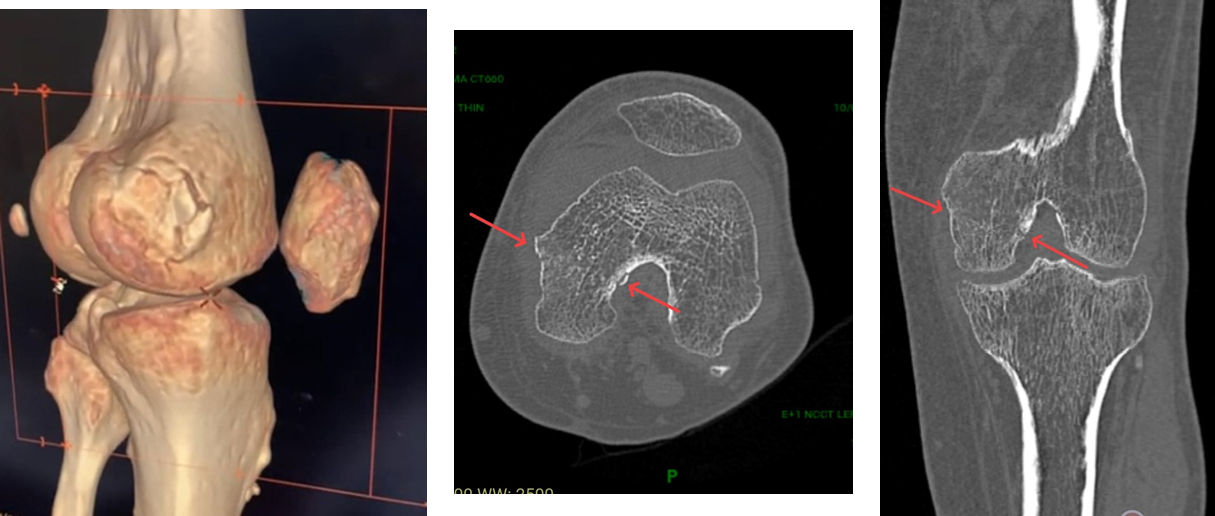

Figure 2: Non-contrast computed tomography scan left knee.

Non-contrast computed tomography (NCCT) and MRI left knee

The NCCT left knee (Fig. 2) was suggestive of an undisplaced fracture of the medial femoral condyle (Hoffa’s fracture).